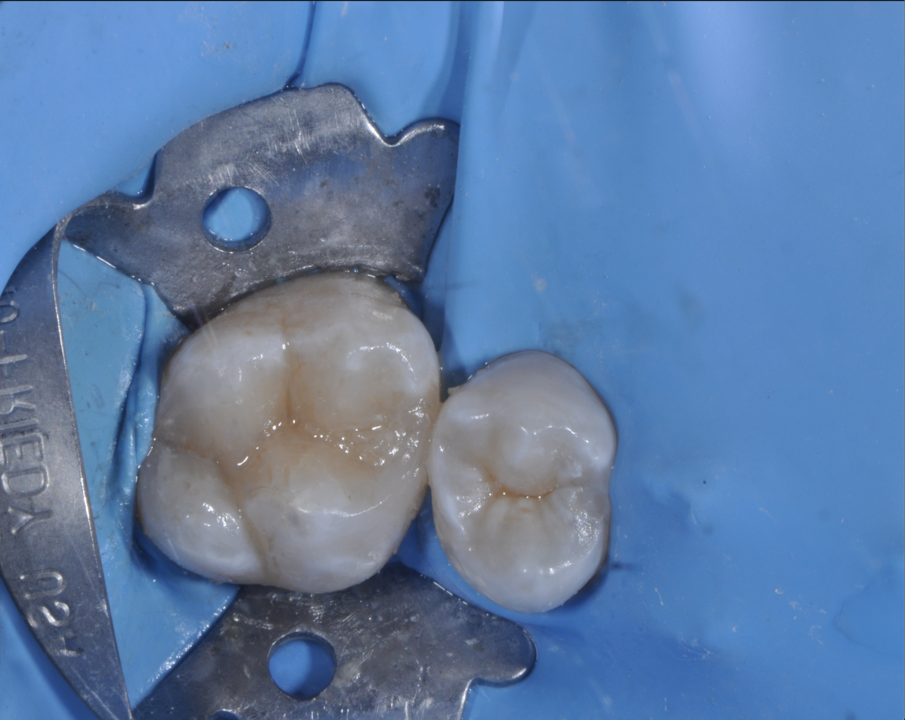

Un paziente di anni 45 giunge in urgenza lamentando un forte dolore in corrispondenza dell’emiarcata mascellare di destra. L’esame anamnestico rivela che il dolore è di tipo pulsante ed è soprattutto notturno. L’esame clinico evidenzia la presenza di un grosso restauro in composito, che era stato effettuato circa 5 anni prima, a livello dell’elemento dentario 2.6; il restauro è infiltrato occlusalmente in più punti. L’elemento in questione risulta dolente alla masticazione; il test di vitalità al freddo esacerba un dolore acuto e prolungato scatenando la sintomatologia lamentata dal paziente. L’esame radiografico di tipo periapicale (Fig. 1) conferma la presenza di infiltrazione cariosa sul fondo della cavità; non evidenzia la presenza di visibili alterazioni a livello del periapice. Viene fatta diagnosi di pulpite acuta e il piano terapeutico prevede il trattamento endodontico ortogrado.

Fig. 1 - Rx periapicale preoperatoria del 2.6.

Il restauro post-endodontico è stato eseguito attraverso ricostruzione diretta in materiale composito con parziale ricopertura delle cuspidi, in attesa di restauro indiretto (Overlay) a ricoprimento cuspidale, non appena le possibilità economiche del paziente lo permetteranno (Figg. 5-7).

Fig. 6 - Foto occlusale intraoperatoria del restauro diretto finalizzato.

Fig. 7 - Foto intraoperatoria del restauro diretto finalizzato e controllo occlusale.